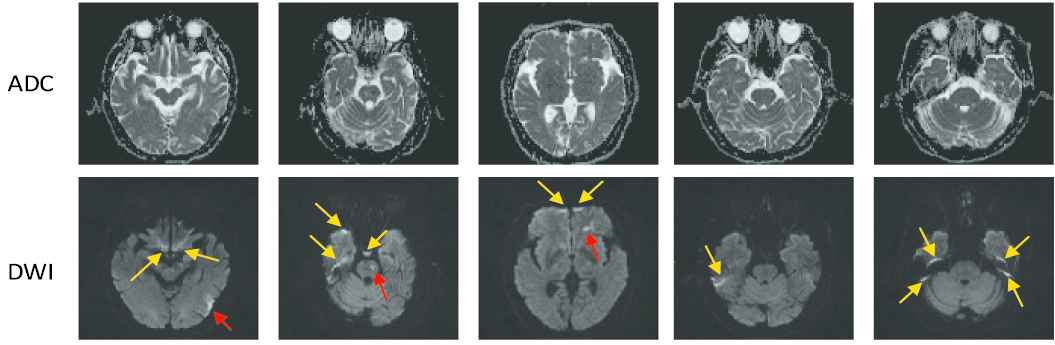

Typically in a CNN, millions of parameters have to be tuned, and therefore a massive amount of images with accurate annotations are required. For instance, Sharma et al. [7] used 165 fully-labeled subjects for organ segmentation, and Zhang et al. [12] collected 152 fully-labeled subjects for lesion segmentation. Different from the images in the ImageNet [13] and COCO [14] dataset which can be easily obtained from the Internet and labeled by the ordinary people, the medical images have to be acquired by special equipment, and many well-trained clinicians are further required to precisely annotate the labels. More importantly, to perform image segmentation, most methods require pixel-by-pixel annotations to train the CNN [5,10,1522]. For instance, in the AIS lesion segmentation task, most methods [12,23,24] required subjects with pixel-wise labels as shown in Figure 2, where each pixel was annotated as normal or lesion. Obviously, annotating the pixel-level labels are labor-intensive and time-consuming, making it even difficult to establish a large dataset. This motivates us to develop a segmentation method by using much simpler annotations. One of the simpler annotations is just annotating whether each slice incorporates lesions or not, as shown in Figure 3. Hereafter, we term this simpler annotation as weak annotation, and the data samples with weak annotations as weakly-labeled. Since the clinicians only require annotating whether each slice includes AIS lesions or not, the annotation cost can be significantly reduced, making it easier to collect a large amount of labeled data samples.

Figure 3

Examples of the weakly-labeled subjects. The first two rows show apparent diffusion coefficient (ADC) slices and their corresponding diffusion-weighted image (DWI) slices. The third row shows the annotations, “yes” indicates that the slice has lesion and “no” indicates the opposite.